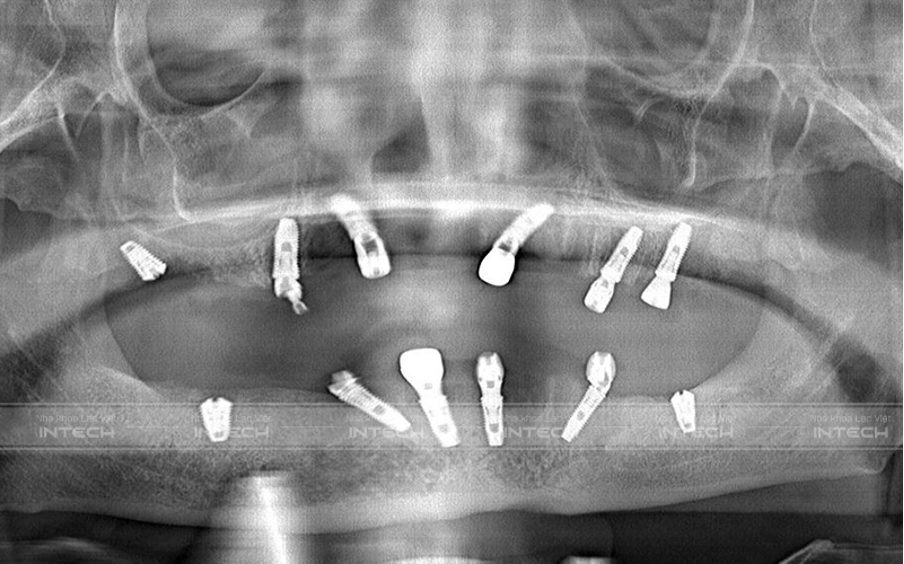

Hình ảnh phim Panorama của chú Nguyễn Duy Khích sau cấy ghép Implant All-on-6 toàn 2 hàm

Sau khi cấy ghép Implant, bác sĩ đã hẹn lịch lắp hàm tạm để giúp bệnh nhân có thể ăn nhai trong thời gian chờ đợi lắp hàm cố định.